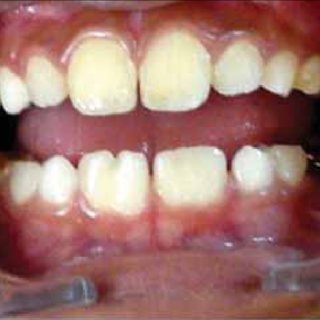

The pattern of caries in primary molars, specifically the maxillary incisors and first molars, is thought to be related to the eruption times of primary teeth and the acquisition of cariogenic bacteria (Xu et al., 2014). Children who develop caries before 2.5 years of age typically exhibit decay on the smooth surfaces of maxillary incisors and occlusal fissures of the first molar teeth (Xu et al., 2014).